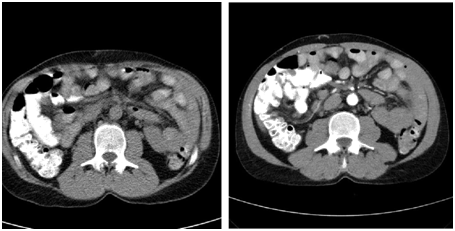

Over a few months, he was complaining of intermittent haematuria with a bulge noticed at the right lower loin, Ultrasound was done in April 2015; and revealed a big mass in the right old transplant kidney (see image 1A, 1B). CT scan with contrast was done (image 2A, 2B), and revealed a large lobulated outlines heterogeneously enhancing mass arising from the right iliac fossa of the transplanted kidney (measures 8.7x 6.9x11.5cm in diameter) with local invasion, lungs metastasis and right common iliac vein tumor thrombus. Due to above finding patient underwent right allograft nephrectomy, with uneventful post-operative course. Biopsy of the transplanted kidney consists with clear renal cell carcinoma. His immunosuppression had been modulated by stopping Mycophenolate and replacing cyclosporine by Everolimus. He is also under oncology follow up (Figure 1a,1b & 2a,2b).

Figure 2a & 2b: Revealed a large lobulated outlines heterogeneously enhancing mass arising from the iliac fossa of transplanted kidney (measures 8.7x6.9x11.5cm in diameter).